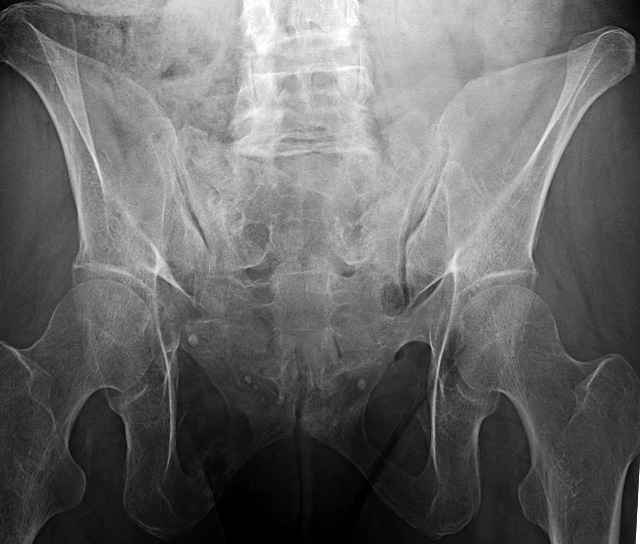

hello everyone, attached are images of a 59 yo female, admitted today after motor vehicle collision. Pt states her pelvis has been very painful ever since she fell on her buttocks from ground level a little over a year ago. medical history significant for scleroderma, raynauds syndrome, and COPD. no past surgeries.

pt states she is very limited in walking ability secondary to pain. she requires a cane or a walker. friends and family do her shopping. the pain is localized primarily around left upper groin. she points to the rami region.

the question is if her medical history is contributing to the nonunions, and if anyone would consider surgical intervention, or is there some other successful intervention?

I’ve operated on 30-35 similar symptomatic patients... usually females in that same age range and most with prior trauma and then with sustained chronic activity related pain due to presumed insufficient healing and resultant ring instability (enough to hurt but not displace too much)...almost all have xray evidence of most of us would consider “hypertrophic” ramus nonunions, and most all have some form of sacral or other posterior ring corresponding injury.

If you examine them for mechanical ring instability, you’ll feel them collapse in your hands as you do... most are overweight to fat to downright obese so the mechanical examination can be a real challenge, but when you anesthetize them you can repeat it under fluoroscopy and see the ramus collapse and displace.

I’ve always inserted/packed/filled them up with medullary ramus screws anteriorly and then filled them posteriorly with multiple iliosacral screws at multiple levels as possible based on numerous clinical osteological factors.